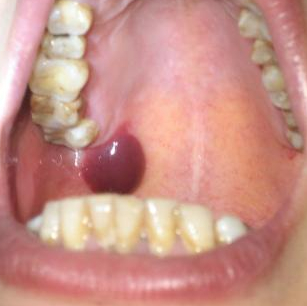

口腔血泡 (9)

口腔血泡 (8)

口腔血泡 (7)

口腔血泡 (6)

口腔血泡 (53)

口腔血泡 (52)

口腔血泡 (51)

口腔血泡 (50)

口腔血泡 (5)

口腔血泡 (49)